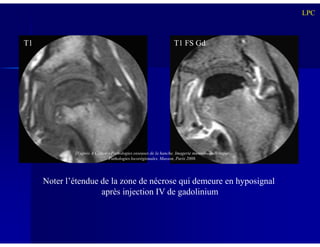

IRM

Intérêt diagnostique:

- Diagnostic précoce de nécrose épiphysaire

(hypointense en T1, signal variable en T2) alors que

les RX sont normales

LPC

- Dissection(s) sous-chondrale(s)

Intérêt pronostique:

- Précise l’extension de la nécrose au sein de la tête

fémorale (séquences dynamiques après gadolinium

± soustraction +++)

T1 T1 FS Gd

Noter l’étendue de la zone de nécrose qui demeure en hyposignal

après injection IV de gadolinium

D’après A Cotten – Pathologies osseuses de la hanche. Imagerie musculosquelettique.

Pathologies locorégionales. Masson, Paris 2008.